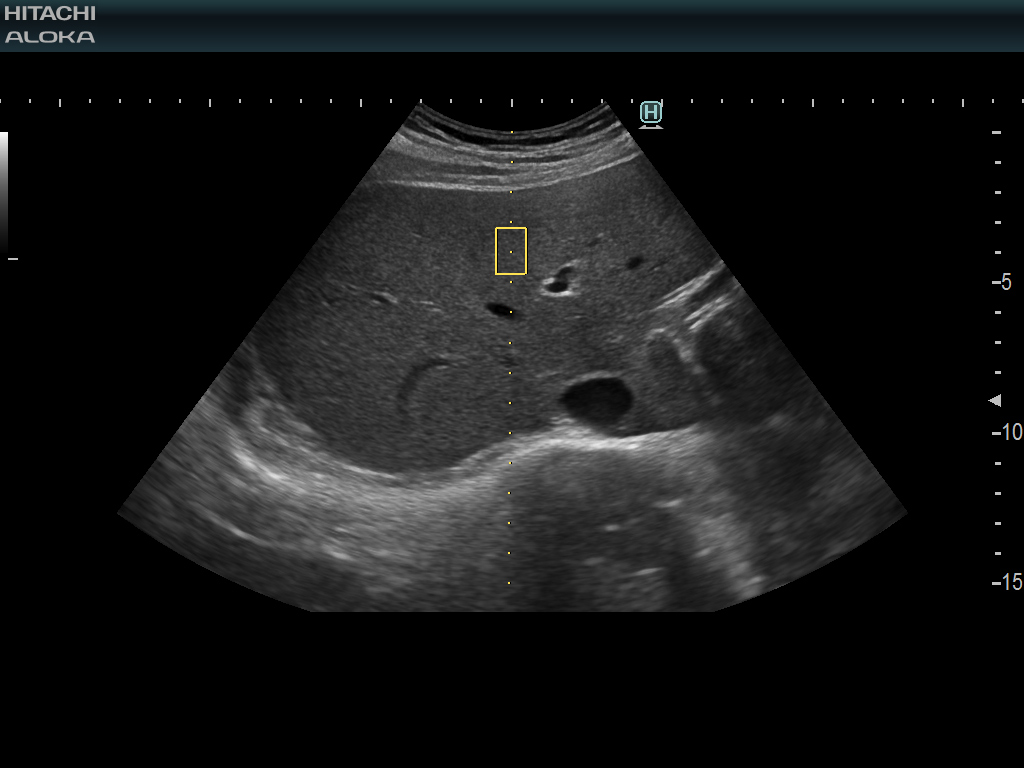

4G CMUT는 심박 기관 및 혈관을 포함한 전신 검사에 사용할 수 있습니다. 이러한 경우 장 벽의 두께와 염증 과정을 묘사합니다.